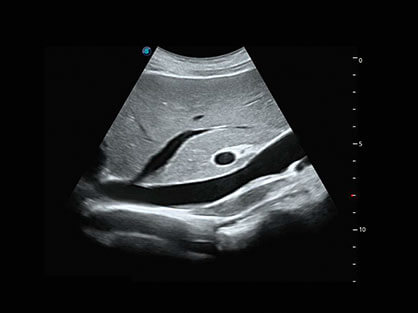

卵泡结构的自动识别和测量,可显示多组测量数据。